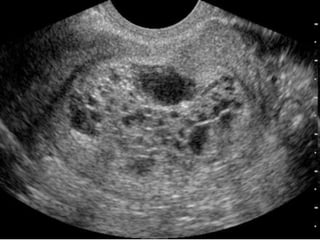

RMI score for ovarian CA

Feature                      RMI 1 Score                  RMI 2 Score

Ultrasound features:         0= none                      0= none

• multilocular cyst             1= one abnormality           1= one abnormality

• solid areas                   3= two or more               4= two or more

• bilateral lesions             abnormalities                abnormalities

• scites

• intra-abdominal

metastases

Premenopausal                1                            1

Postmenopausal               3                            4

CA125                        U/ml                         U/ml

RMI score = ultrasound score x menopausal score x CA125 level in U/ml.

The RMI scoring system is the method of choice for predicting whether or not an

ovarian mass is likely to be malignant.

Women with an RMI score >200 should be referred to a centre

with experience in ovarian cancer surgery. Evidence grade 2+